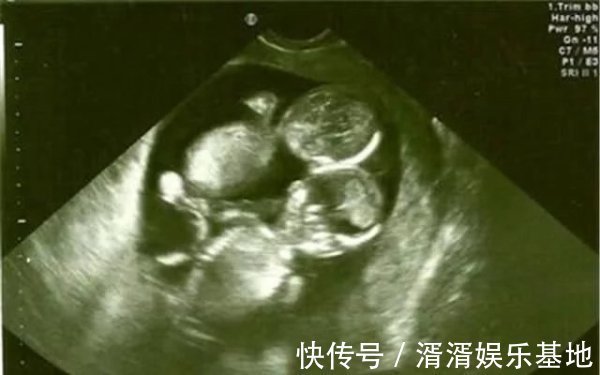

然而怀孕第五个月排畸检查却让全家人掉入了谷底,医生告知这是一个连体婴儿,脑袋连在一起了,建议立马做引产手术。不然生下来不但拖累家庭,对孩子也是一种不负责。车女士和老公瞬间感觉到整个天都塌了,此时孩子已经有胎心了,陈女士能明显感觉到宝宝强有力的跳动。

半个小时后,子宫被划开了,医生却惊喜欢呼,双胞胎并没有连体,是一对龙凤胎,十分健康。车女士听后顿时忍不住哭泣起来,心里的委屈一下子全部控制不住发泄出来,没有人知道整个孕期她是怎么过来,承受了多大的心理压力。医生说做四维彩超的时候,刚好两个胎儿的头紧紧靠在一起,所以被误认为是连体婴,没想到却是兄妹情深,相互相依。产房外的家属得知后也是相拥而泣,爸爸更是对两个更出生的婴儿说,以后一定要好好孝顺你妈,是她的坚持才有你们俩。